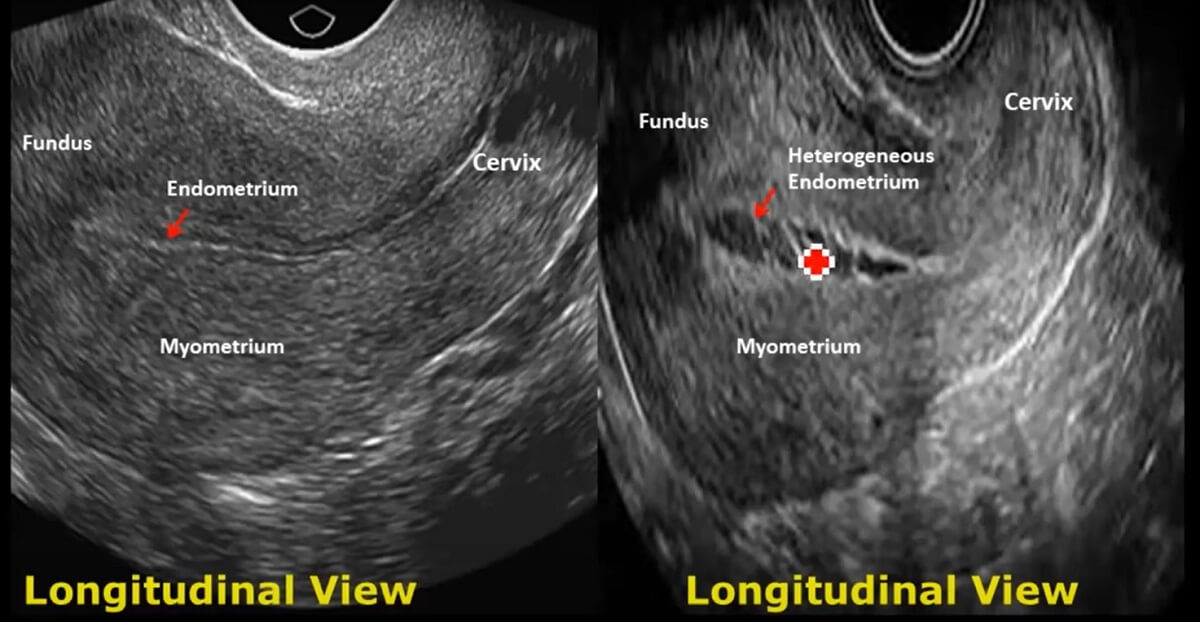

- Debljinu, ehogenost (tamnoća ili svetlost slike u vezi sa gustinom tkiva) i prisustvo tečnosti ili masa u endometrijumu, miometrijumu (mišićno tkivo materice), jajovodima, ili u ili blizu bešike;